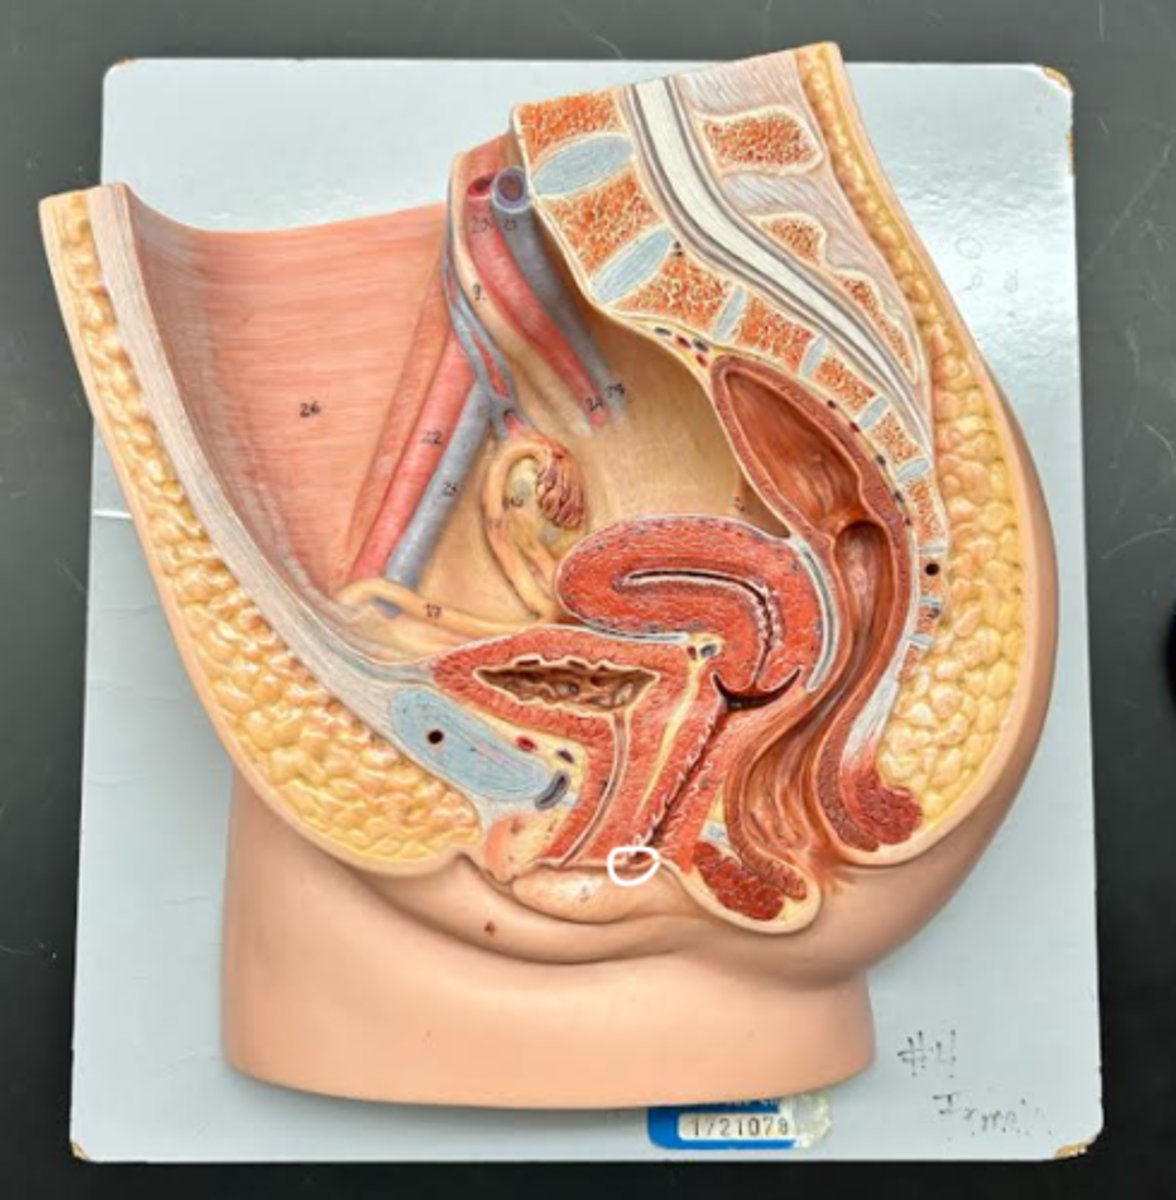

Vagina

Vaginal orifice

Hymen

Vaginal fornix

Cervix

Internal os

Cervical canal

External os

Labia majora

Labia minora

Prepuce

Vestibule

Clitoris

External urethral orifice